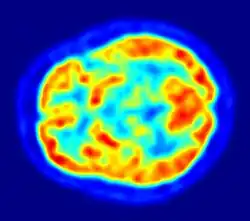

F-FDG (fluorodeoxyglucose). The normal brain and kidneys are labeled, and radioactive urine from breakdown of the FDG is seen in the bladder. In addition, a large metastatic tumor mass from colon cancer is seen in the liver.

PET scanning with the radiotracer [18F]fluorodeoxyglucose (FDG) is widely used in clinical oncology. FDG is a glucose analog that is taken up by glucose-using cells and phosphorylated by hexokinase (whose mitochondrial form is significantly elevated in rapidly growing malignant tumors).[6] Metabolic trapping of the radioactive glucose molecule allows the PET scan to be utilized. The concentrations of imaged FDG tracer indicate tissue metabolic activity as it corresponds to the regional glucose uptake. FDG is used to explore the possibility of cancer spreading to other body sites (cancer metastasis). These FDG PET scans for detecting cancer metastasis are the most common in standard medical care (representing 90% of current scans). The same tracer may also be used for the diagnosis of types of dementia. Less often, other radioactive tracers, usually but not always labelled with fluorine-18 (18F), are used to image the tissue concentration of different kinds of molecules of interest inside the body.

Because the hydroxy group that is replaced by fluorine-18 to generate FDG is required for the next step in glucose metabolism in all cells, no further reactions occur in FDG. Furthermore, most tissues (with the notable exception of liver and kidneys) cannot remove the phosphate added by hexokinase. This means that FDG will remain trapped in any cell that takes it up until it decays, since phosphorylated sugars, due to their ionic charge, cannot exit from the cell. This results in intense radiolabeling of tissues with high glucose uptake, such as the normal brain, liver, kidneys, and most cancers, which have a higher glucose uptake than most normal tissue due to the Warburg effect. As a result, FDG-PET can be used for diagnosis, staging, and monitoring treatment of cancers, particularly in Hodgkin lymphoma,[7] non-Hodgkin lymphoma,[8] and lung cancer.[9][10][11]